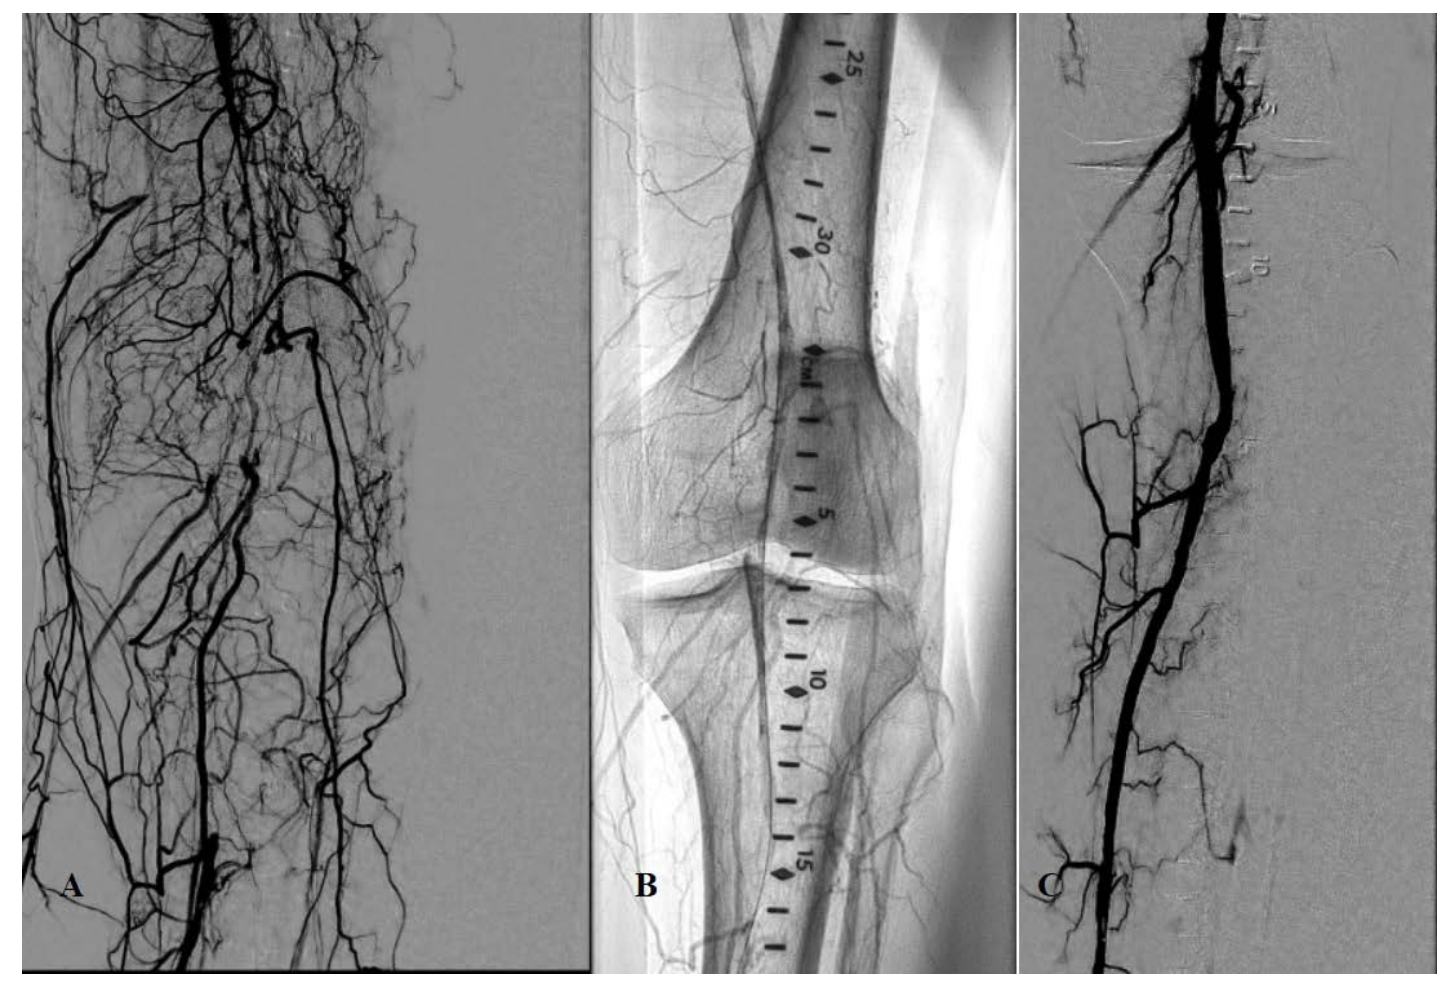

Patient underwent peripheral angiography and baseline images confirmed the CTA findings (Figure 1A). The lesion was crossed successfully with a CXI (Cook) 0.018” crossing catheter and a 12 gm Approach wire (Cook). The wire was later changed to a Spartacore wire (Abbott). Since we suspected an underlying thrombotic event and there is very little room for an embolic filter protection, we elected to use the Auryon™ laser with aspiration system to treat the lesion. Intravascular ultrasound (IVUS) was initially performed. The Eagle Eye Platinum IVUS catheter (Philips) was used (Figure 2A). The 1.5 laser was initially used and was taken all the way down into the posterior tibialis artery (PT) which also was proximally occluded. The peroneal and anterior tibialis arteries were occluded at their origin. Following this we proceeded with the use of the laser 2.0 (with aspiration) to treat the distal SFA and the popliteal. IVUS sizing of the PT showed a vessel of 3.8 mm on average in diameter. The 4.0 mm Lutonix (Bard/BD) drug coated balloon (DCB) was used to treat the PT into the tibioperoneal trunk. This was followed by Lutonix treatment to the distal left SFA and popliteal. DCB were used for a total of 3 minutes’ inflation each. Brisk flow was established all the way to the foot (Figure 1). No complications or angiographic dissections were noted and less than 100 cc of blood was aspirated. Stenting was not required.